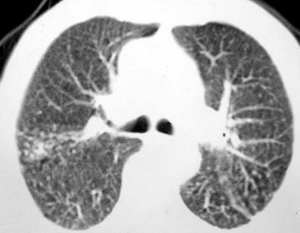

以下是引用sdqzwyx在2005-11-7 19:59:00的发言:[br]双肺弥漫大小不等的粟粒状结节影;肺纹理走行失去自然,粗细不均,边缘不规则,小叶间隔增厚;左上肺示不规则形致密影,从斑块边缘向周围伸出长短不一的致密索条影,临近的血管、支气管和叶间胸膜等结构受牵拉移位;左下肺示不规则团块状影,其内示空洞,洞内壁尚光整,左侧胸腔积液。右肺下叶背段亦示部分病灶融合。双肺可见局限性肺气肿。[br]诊断:结合病史符合三期矽肺表现(少数矽肺纤维斑块内可以形成空洞,一般认为是斑块中央感染引起坏死所致)但尘肺病人易合并肺结核,诊断可为三期+tb。所以此病人应进一步检查是否合并结核。